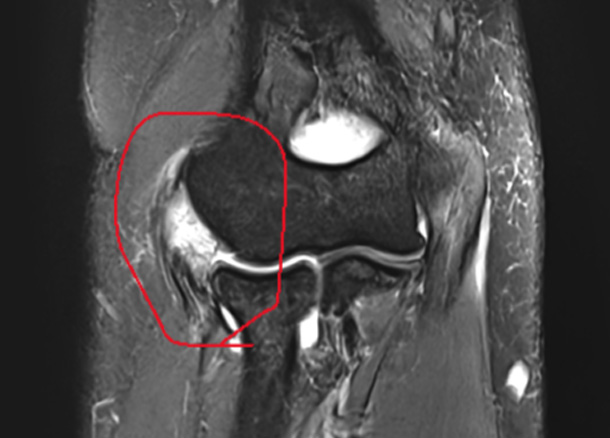

After 수술 후

1년 후 완전 정상화

* 환자에게 받은 소중한 자료입니다.